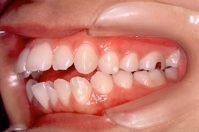

1) 主訴 前歯で咬むことができない

2) 診断名 前歯部開咬